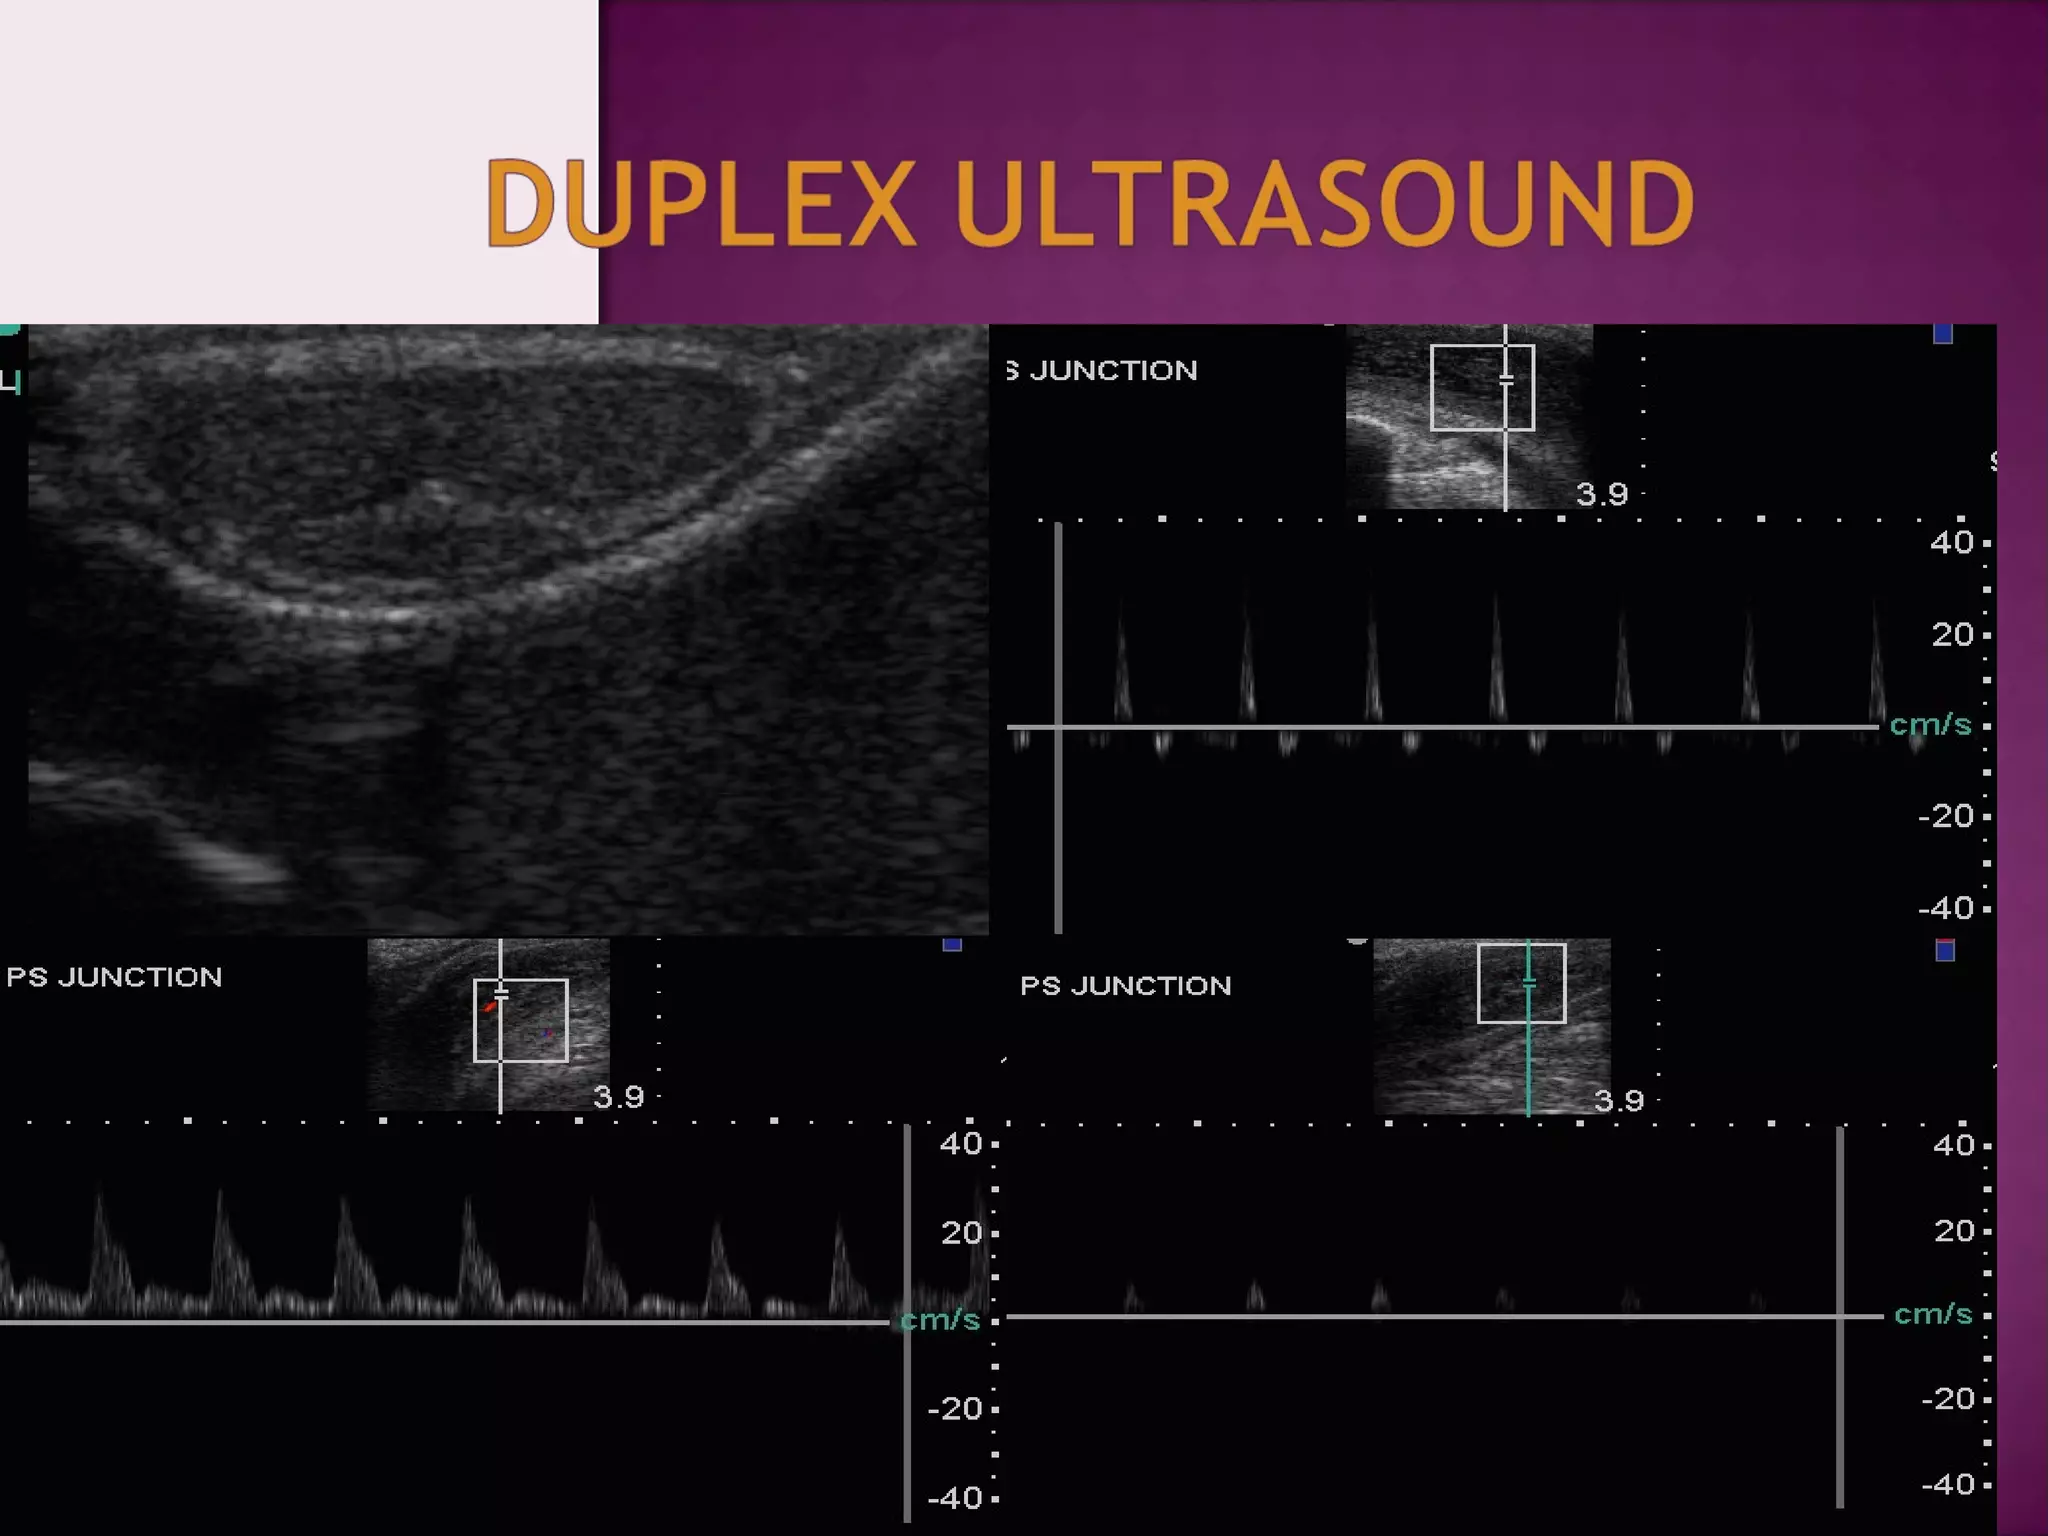

Specialized diagnostic tests

 Vascular studies

- Duplex ultrasound

There is no need to continue vascular investigation

when the duplex examination is normal